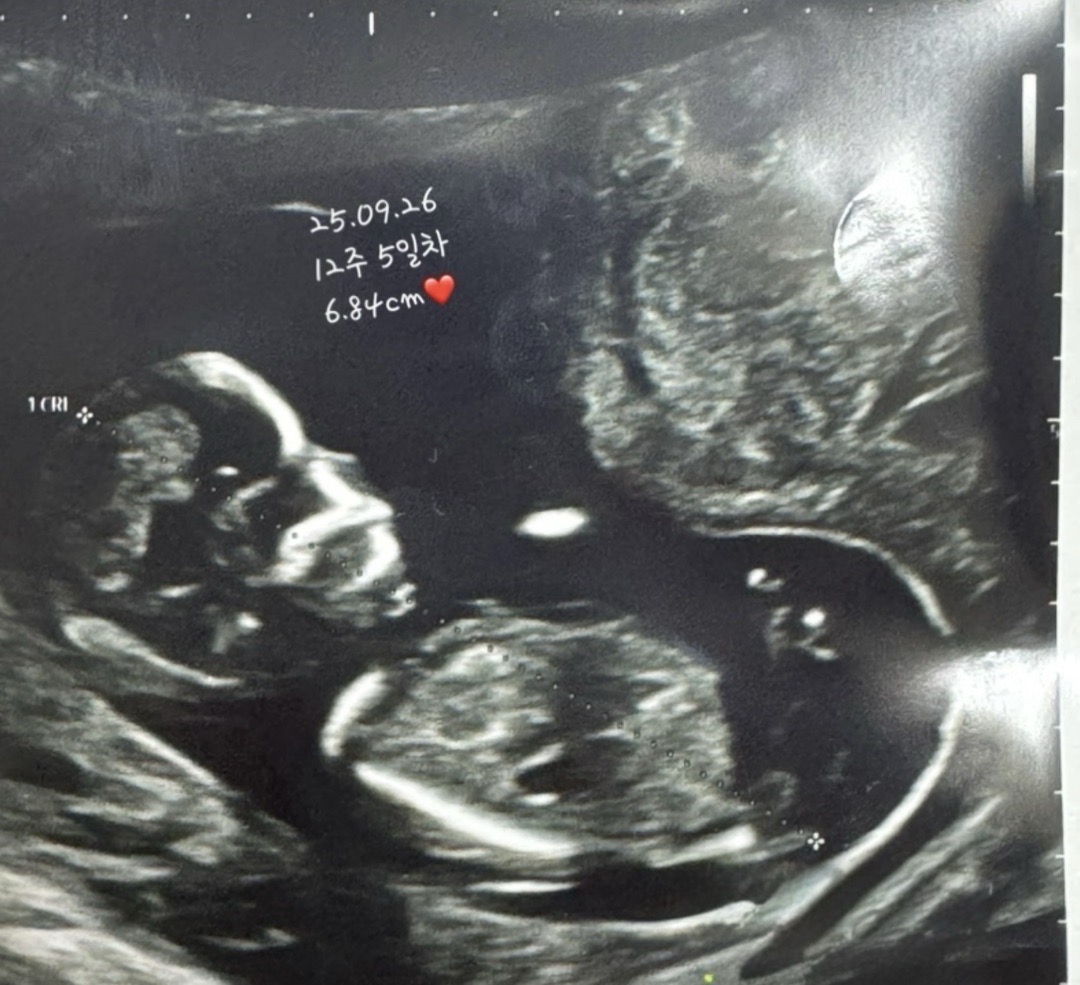

저는 병원갈때마다 초음파사진이 잘 안나오더라구요! 1차 기형아검사때도 10분동안 봤는데 꼬옥 숨어서 안보여주더라구요😂 16주 5일차때 병원가는데 초음파 잘나오는 꿀팁 알려주세요~! 사진은 12주차 기형아검사 사진인데 딸일지 아들일지 기대중입니다🥹❤️